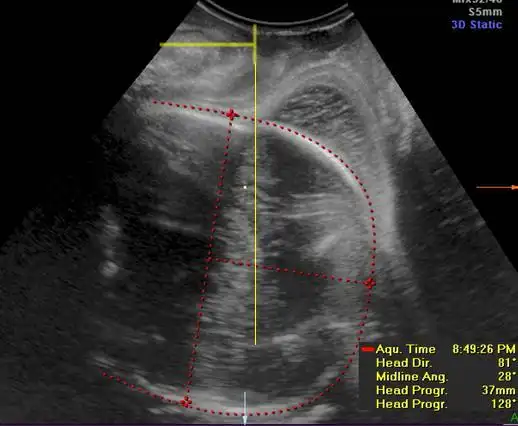

三维超声的产科疾病